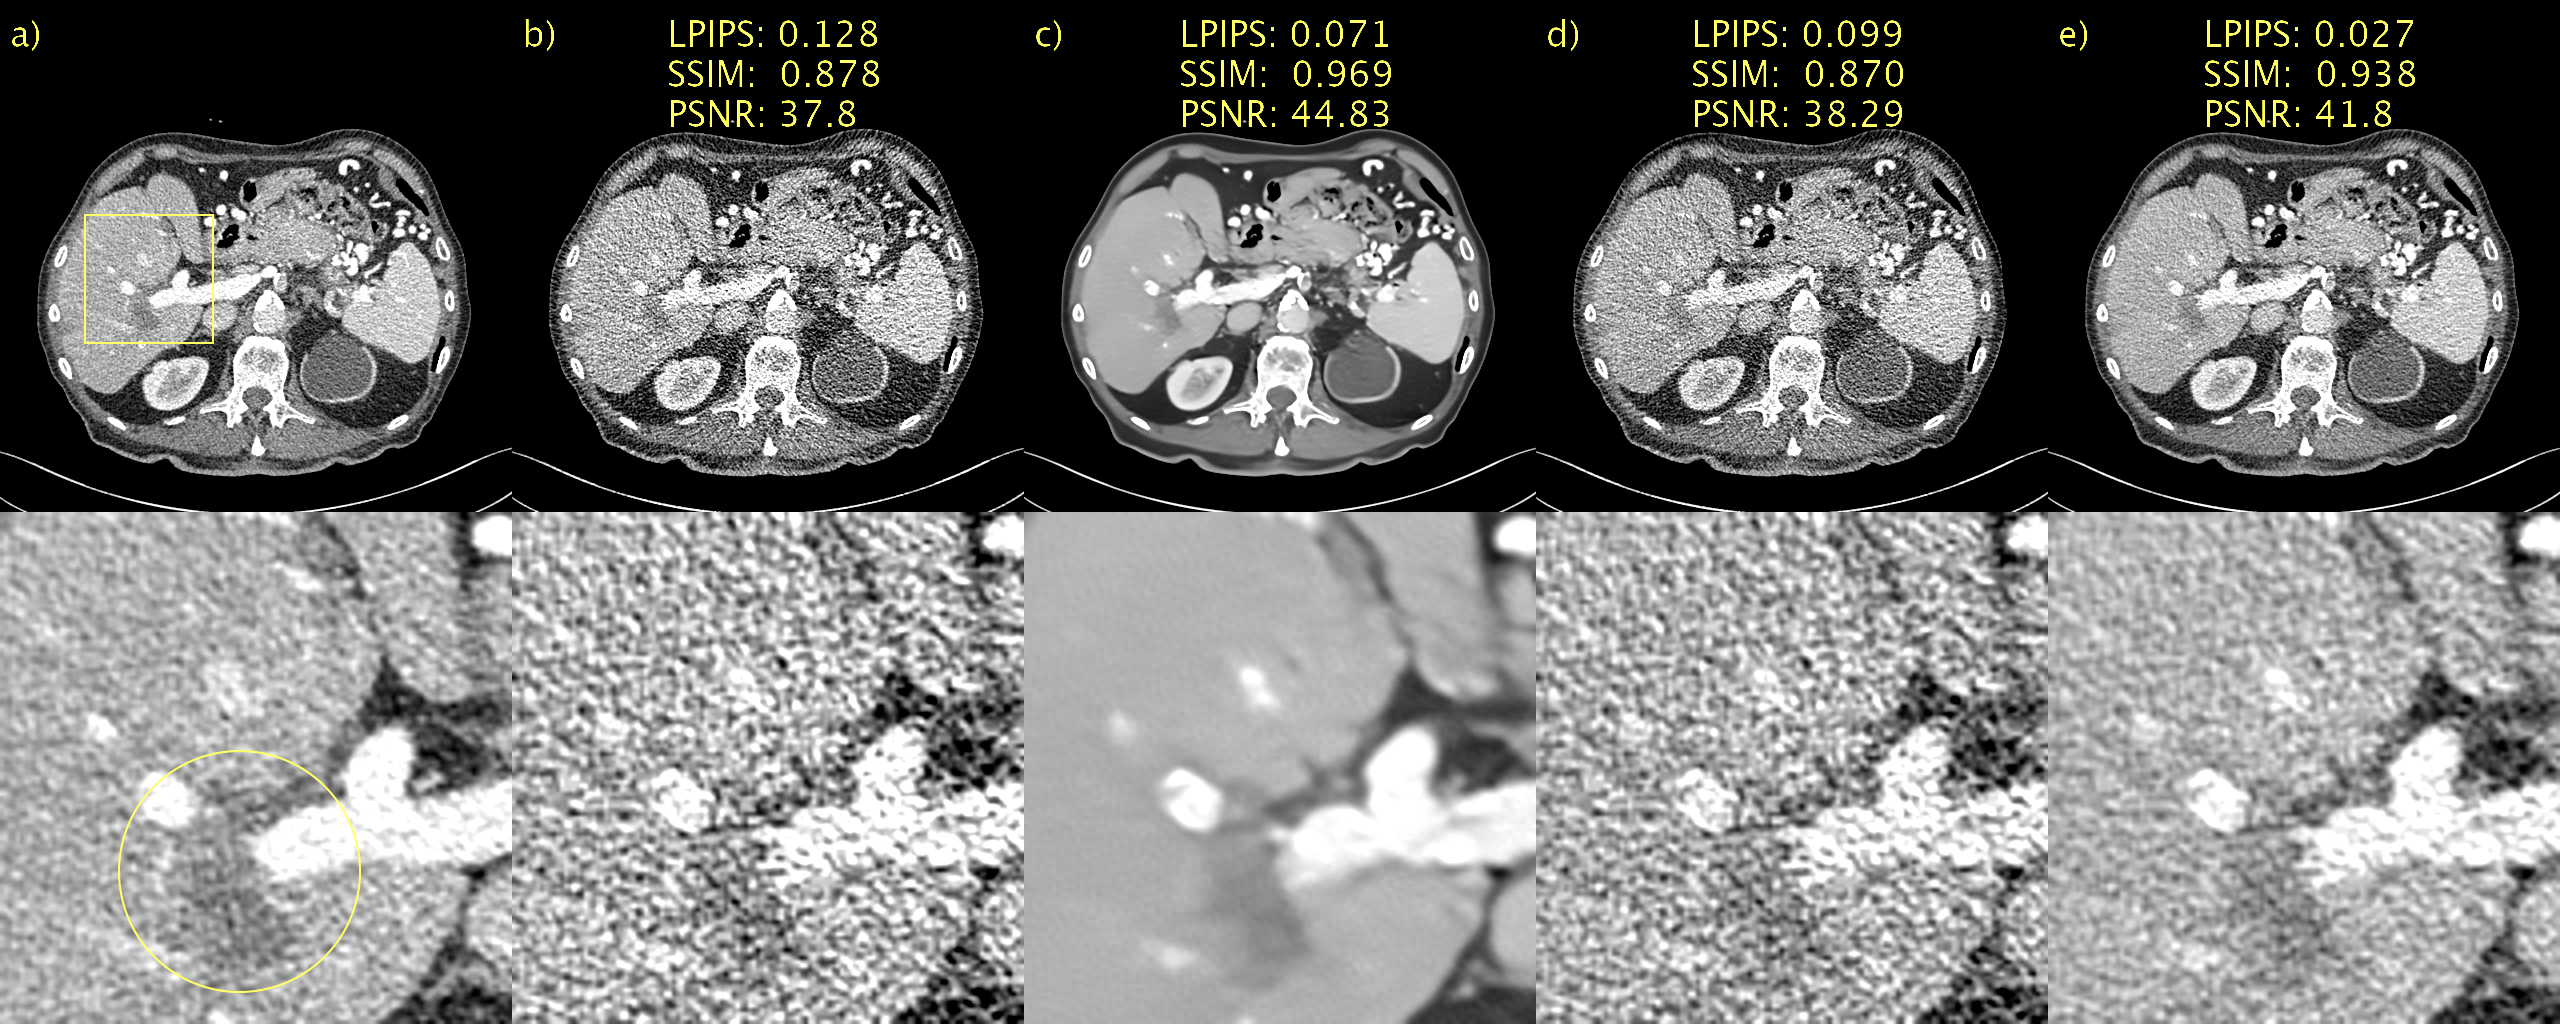

Qualitative results, alongside LPIPS, SSIM, and PSNR, for a representative slice from the Mayo low-dose CT validation data appear in Fig. 1. For the sake of brevity, we show results for the proposed method only for D𝐷D\rightarrow\infty and, best performing, D=128.𝐷128D=128. The former is included as an interesting case since it corresponds to a diffusion model, instead of PFGM++. This patient has a metastasis in the liver and we have included a magnification of this region of interest (ROI) in Fig. 2. a) and b) show the NDCT and LDCT images, respectively for reference. BM3D, shown in c), performs well in terms of noise suppression whilst preserving salient details. Nevertheless, this comes at a cost of artifacts that make the image appear a somewhat smudgy. WGAN-VGG, CD, and PPFM, all supervised methods, shown in d), e) and f), all suppress noise effectively and keep key details intact. We have overlaid a yellow arrow to point out a detail that appears in CD, shown e), but in none of the other images, including NDCT and LDCT. It appears that CD has added a feature into the image that appears realistic, but which we know is not genuine, given that we have the LDCT and NDCT images as reference. Such inaccurate removal or addition of details is loosely referred to as hallucination [2]. Noise2Void, shown in g), seems to in essence reproduce the LDCT image. However, quantitatively there is a marginal improvement. However, as shown in i), the proposed method (with D=128𝐷128D=128) effectively suppresses the noise whilst keeping salient features intact. Qualitatively, it is difficult to discriminate between the proposed method with D=128,𝐷128D=128, which is an unsupervised method, and PPFM, shown in f), a supervised method. Quantitatively for this particular slice, we can see that PPFM performs slightly better. Comparing D𝐷D\rightarrow\infty, shown in h), with D=128𝐷128D=128 in i) demonstrates the performance gains afforded by the PFGM++ framework. In particular, the proposed method with D𝐷D\rightarrow\infty appears over-smoothed and somewhat blurred.

Figure 1: Results on the Mayo low-dose CT dataset. Abdomen image with a metastasis in the liver. a) NDCT, b) LDCT, c) BM3D, d) WGAN-VGG, e) CD, f) PPFM, g) Noise2Void h) D𝐷D\rightarrow\infty i) D=128𝐷128D=128. Yellow box indicating ROI shown in Fig. 2. 1 mm-slices. Window setting [-160,240] HU.

Figure 2: ROI in Fig. 1 magnified to emphasize details. a) NDCT, b) LDCT, c) BM3D, d) WGAN-VGG, e) CD, f) PPFM, g) Noise2Void h) D𝐷D\rightarrow\infty i) D=128𝐷128D=128. Yellow circle added to emphasize lesion. 1 mm-slices. Window setting [-160,240] HU.

Results from an ablation study of the proposed sampler are available in Fig. 3. a) and b) show the NDCT and LDCT images for easy reference. In c) we hijack but omit regularization (τ=T1,w=1formulae-sequence𝜏𝑇1𝑤1\tau=T-1,w=1). The result is an image that has been very aggressively denoised. This is a direct consequence of the small T𝑇T and corresponding large step-size. This represents a further clean demonstration of how SSIM and PSNR fail to adequately penalize blurring as c) appears blurry to a human observed yet performs very well according to SSIM and PSNR. LPIPS, on the hand, penalizes this quite heavily. In d), we regularize but employ no hijacking (τ=0,w=0.5formulae-sequence𝜏0𝑤0.5\tau=0,w=0.5). In this case we start with an initial sample from the prior noise distribution. The amount of regularization in this setting seems excessive and we recover an image where 𝒚^𝒄.bold-^𝒚𝒄\bm{\hat{y}}\approx\bm{c}. Finally, in e) we employ hijacking and regularization (τ=T1,w=0.5formulae-sequence𝜏𝑇1𝑤0.5\tau=T-1,w=0.5), resulting in a very pleasing image where 𝒚^𝒚.bold-^𝒚𝒚\bm{\hat{y}}\approx\bm{y}. Consequently, there is a significant reduction (improvement) in LPIPS.

Refer to caption

Figure 3: Ablation study of regularizer used in our proposed sampler. a) NDCT, b) LDCT, c) only hijacking, d) only regularization, e) hijacking and regularization. Yellow circle added to emphasize lesion. 1 mm-slices. Window setting [-160,240] HU.